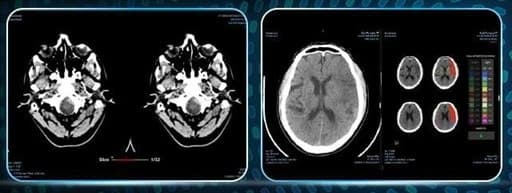

의료AI 기업 제이엘케이의 비조영CT 기반 뇌졸중 분석 솔루션 'JLK NCCT'가 미국 식품의약국(FDA)으로부터 시판 허가를 획득했습니다.

이 솔루션은 뇌졸중 진료 과정에서 가장 먼저 시행되는 비조영CT 단계에서 의심 환자의 신속한 식별과 우선순위 설정을 지원하는 AI 기술입니다. JLK NCCT는 뇌출혈 의심 환자를 선별하고, 시술이 필요한 대혈관폐색(LVO) 의심 환자를 분류하는 것이 특징입니다.

특히 NCCT 단계에서도 대혈관폐색을 조기에 식별하여 응급 단계에서 신속한 환자 분류와 대응을 지원합니다. 이는 뇌졸중 치료에서 중요한 '골든타임' 확보에 핵심적인 역할을 할 것으로 기대됩니다.